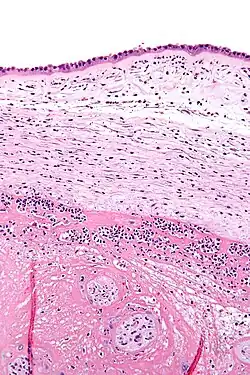

Une chorioamniotite est une inflammation des membranes fœtales, l'amnios et le chorion, généralement causée par une infection bactérienne[1].